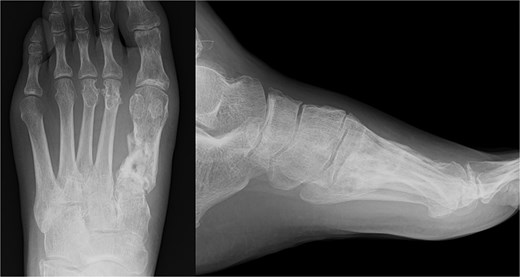

We performed surgery in two stages, owing to the poor condition of the skin. In the first stage, we performed screw fixation for the tibial pilon fracture and plate fixation for the distal fibular fracture. For the first-metatarsal fracture, half pins for external fixation were inserted into the first proximal phalanx, first metatarsal, medial cuneiform, and navicular bone. The external fixator (The Small External Fixation System, Synthes, Oberdorf, Switzerland) was stabilized with the first reduction in the metatarsal shortening deformity (Fig. 2). One week later, the second-stage surgery was performed after the swelling of soft tissues on the dorsum of the foot had improved. A longitudinal skin incision was made on the dorsum of the first metatarsal, and a fusion plate (Variable Angle LCP Forefoot/Midfoot system, Synthes) was placed on the dorsal aspect of the first metatarsal and the medial cuneiform. Three screws were inserted into the medial cuneiform, and four screws were inserted into the distal end of the first metatarsal. Postoperative radiography and CT images are shown in Fig. 3.

Radiography (a, b) and computed tomography (c) images immediately after the second surgery.